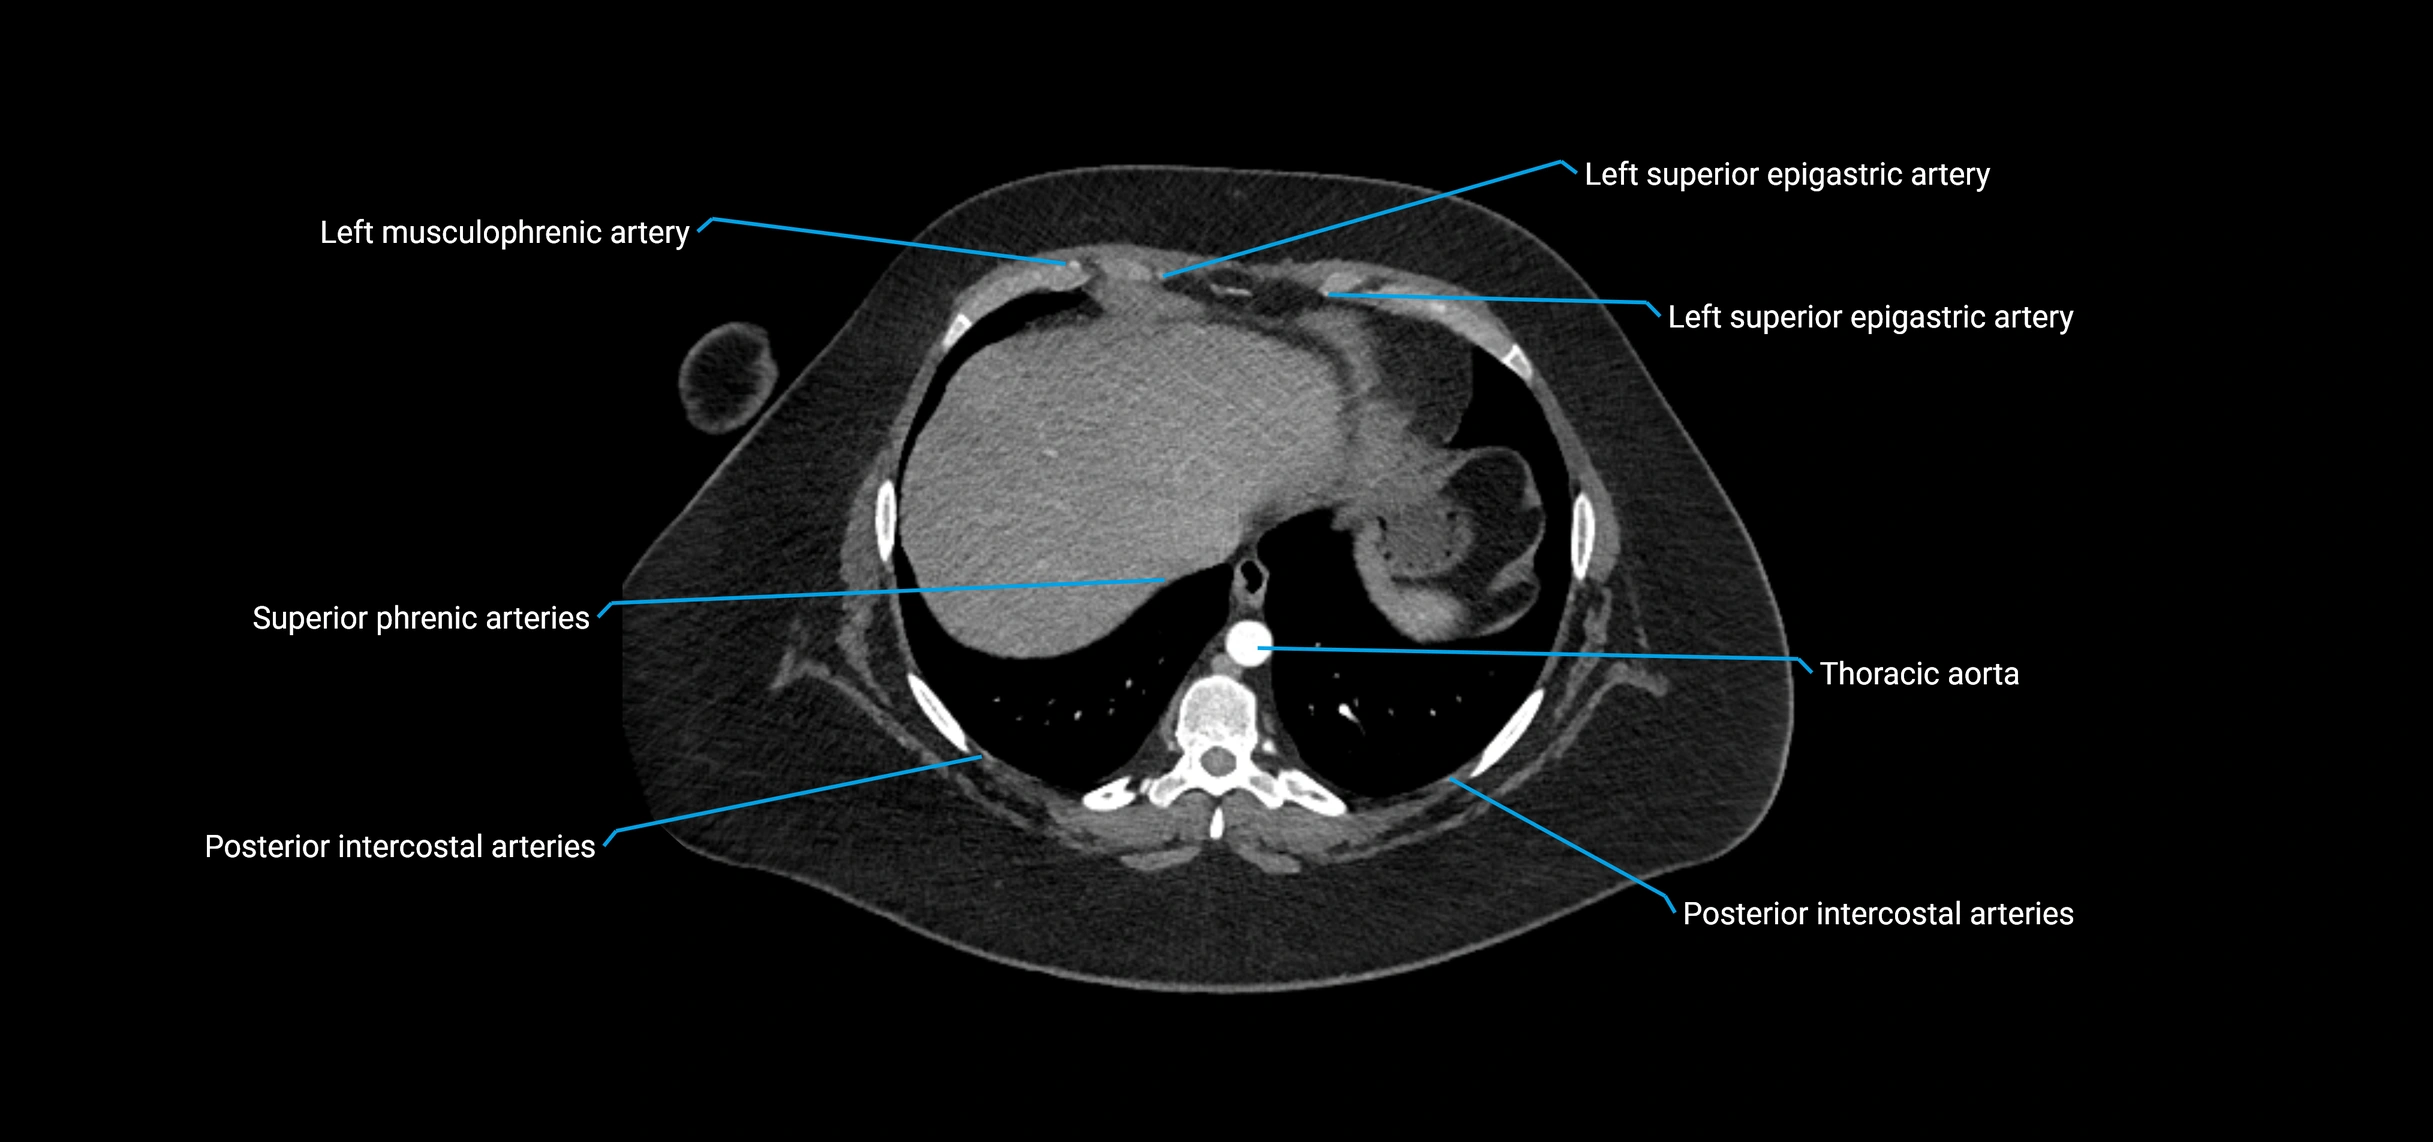

CT images

image

CT Appearance

Non-contrast CT:

• Appears as a tubular soft tissue structure anterior to vertebral bodies

• Calcified atherosclerotic plaques appear as hyperdense foci along the wall

• Useful for screening abdominal aortic aneurysm (AAA) size and mural calcification

Contrast-enhanced CT (CTA):

• Gold standard for abdominal aortic imaging

• Provides excellent detail of lumen, wall, aneurysm, thrombus, and branch vessels

• Multiplanar and 3D reconstructions help in aneurysm measurement, stent graft planning, and dissection evaluation

• Detects acute rupture, traumatic injury, or occlusion with high sensitivity